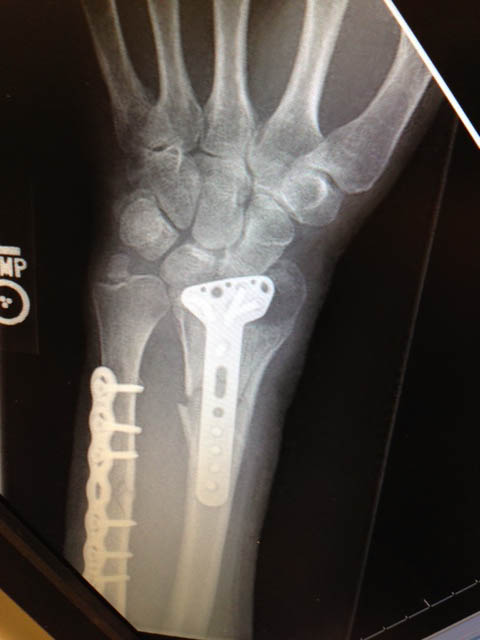

The ambulance arrived shortly and Ness was transported to a local hospital, which quickly sent him to a major trauma center in Minneapolis. The doctors set his arm, which was broken in 15 places, and ended up having to amputate the finger. His surgery last five-and-a-half hours.

“They were able to put it all back and the doctor did an excellent job,” said Ness. “I’m the luckiest man in the world. Somebody else was taking care of me, believe me.”

Ness confirmed the surgery to repair his arm required 18 titanium screws. The recovery, he admits, required a positive spirit.